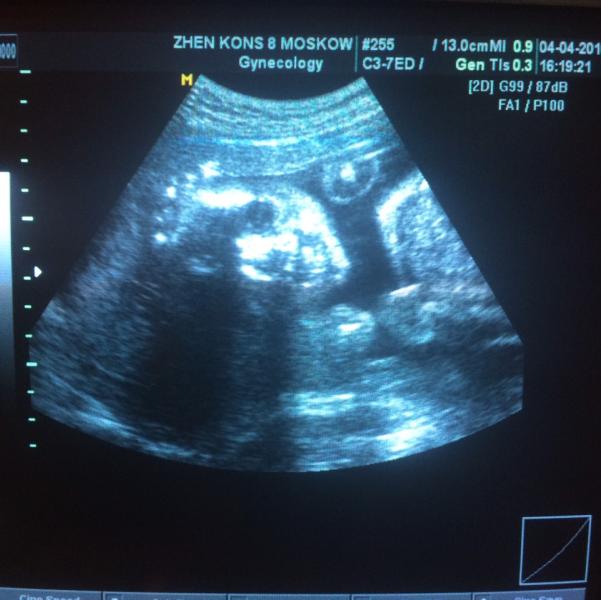

Была сегодня на УЗИ + доплер, кровотоки в норме, размеры крошки соответствуют нашим неделям, шейка матки тоже в норме, а то я переживала, что может быть короткая из-за чрезмерной активности 😰 лежит мартышка поперёк, поэтому мне и не удобно, два раза толкнула узистку в штуку, которой она водит по животу (беременный мозг забыл, как это называется 😂), лежит скромно и прикрывает ручками все самое важное, но подтвердили, что девочка👸🏼 весит 710 гр и кажется ей мало, потому что я всегда хочу жрать, даж...